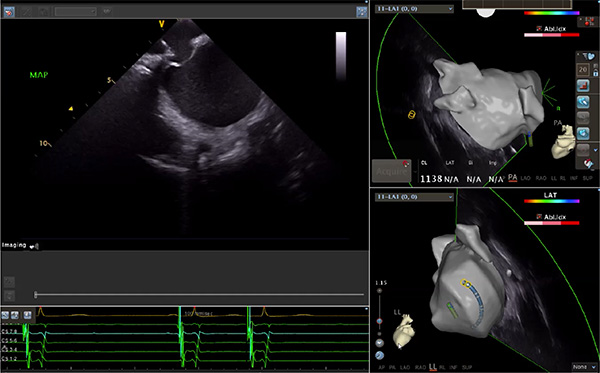

超聲心動圖技術(shù)包括常規(guī)經(jīng)胸超聲(TTE)、經(jīng)食管超聲(TEE)、心腔內(nèi)超聲(ICE)、超聲聲學(xué)造影(MCE)、三維超聲心動圖等,ICE是一種新興技術(shù)——將微型的換能器安裝在心導(dǎo)管的尖端,經(jīng)由外周血管輸送至心腔內(nèi)部,換能器發(fā)射聲波,對心臟及其鄰近組織進(jìn)行實(shí)時高質(zhì)量成像和(或)血流動力學(xué)測定的超聲成像技術(shù)?;诓煌募夹g(shù)原理,心腔內(nèi)超聲導(dǎo)管被分為兩類:機(jī)械旋轉(zhuǎn)式超聲導(dǎo)管和相控陣超聲導(dǎo)管。目前,臨床上主要應(yīng)用的是相控陣超聲導(dǎo)管,ICE成像通過術(shù)者旋轉(zhuǎn)導(dǎo)管及操縱導(dǎo)管手柄上的兩個旋鈕來完成。

ICE門檻高、集成了超聲和圖像處理最前端的技術(shù),是當(dāng)前內(nèi)窺超聲方向最挑戰(zhàn)的領(lǐng)域。不同于傳統(tǒng)接觸式三維重建方法會產(chǎn)生假腔,影響術(shù)者對靶點(diǎn)或結(jié)構(gòu)的判斷,心腔內(nèi)超聲(ICE)可直接顯示心臟結(jié)構(gòu),有助于理解心臟內(nèi)各部位之間的解剖關(guān)系,不僅具有實(shí)時成像、并發(fā)癥監(jiān)測以及良好的耐受性,同時以股靜脈入路,無需全麻或深度鎮(zhèn)靜,日益成為心臟介入手術(shù)中重要輔助工具,被譽(yù)為心臟介入醫(yī)生的“黃金眼”。心腔內(nèi)超聲可用于多種心臟介入手術(shù),潛在患者群體龐大,動脈網(wǎng)測算我國心腔內(nèi)超聲導(dǎo)管市場空間或?qū)⒊?00億元,具有廣闊前景。

隨著心腔內(nèi)超聲的應(yīng)用更廣,性能也在逐漸優(yōu)化,已從二維成像轉(zhuǎn)變?yōu)?strong>三維成像,極大增強(qiáng)了引導(dǎo)及可視化能力。二維心腔內(nèi)超聲支持雙平面或三平面成像,可顯示兩個或三個不同的平面視圖,但醫(yī)生需將這些圖像在腦海中重新構(gòu)建為三維解剖結(jié)構(gòu)。三維心腔內(nèi)超聲則可直接呈現(xiàn)三維解剖結(jié)構(gòu)圖,便于醫(yī)生更輕松地開展手術(shù)。按照產(chǎn)品發(fā)展方向,預(yù)計(jì)心腔內(nèi)超聲還將向更清晰、精準(zhǔn)、多功能等方向發(fā)展。